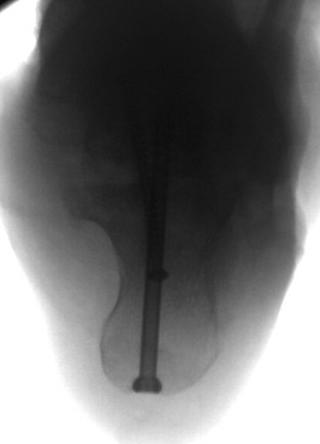

TOTAL ANKLE REPLACEMENT :: ORIF CALCANEUS :: ORIF ANKLE FRACTURE DISLOCATION :: COMPLEX BUNION AND LESSER TOE CORRECTION :: TALUS FRACTURE -1 :: TALUS FRACTURE -2 :: LISFRANC REPAIR :: COMPLEX TRIPLE ARTHRODESIS 1 :: COMPLEX TRIPLE ARTHRODESIS 2 :: MINIMALLY INVASIVE BUNION REPAIR 1 :: MINIMALLY INVASIVE BUNION REPAIR 2 :: ARTHROSCOPIC CARTILAGE REPAIR :: TENEX SPUR DEBRIDEMENT :: Haglunds Debridement and Achilles Repair